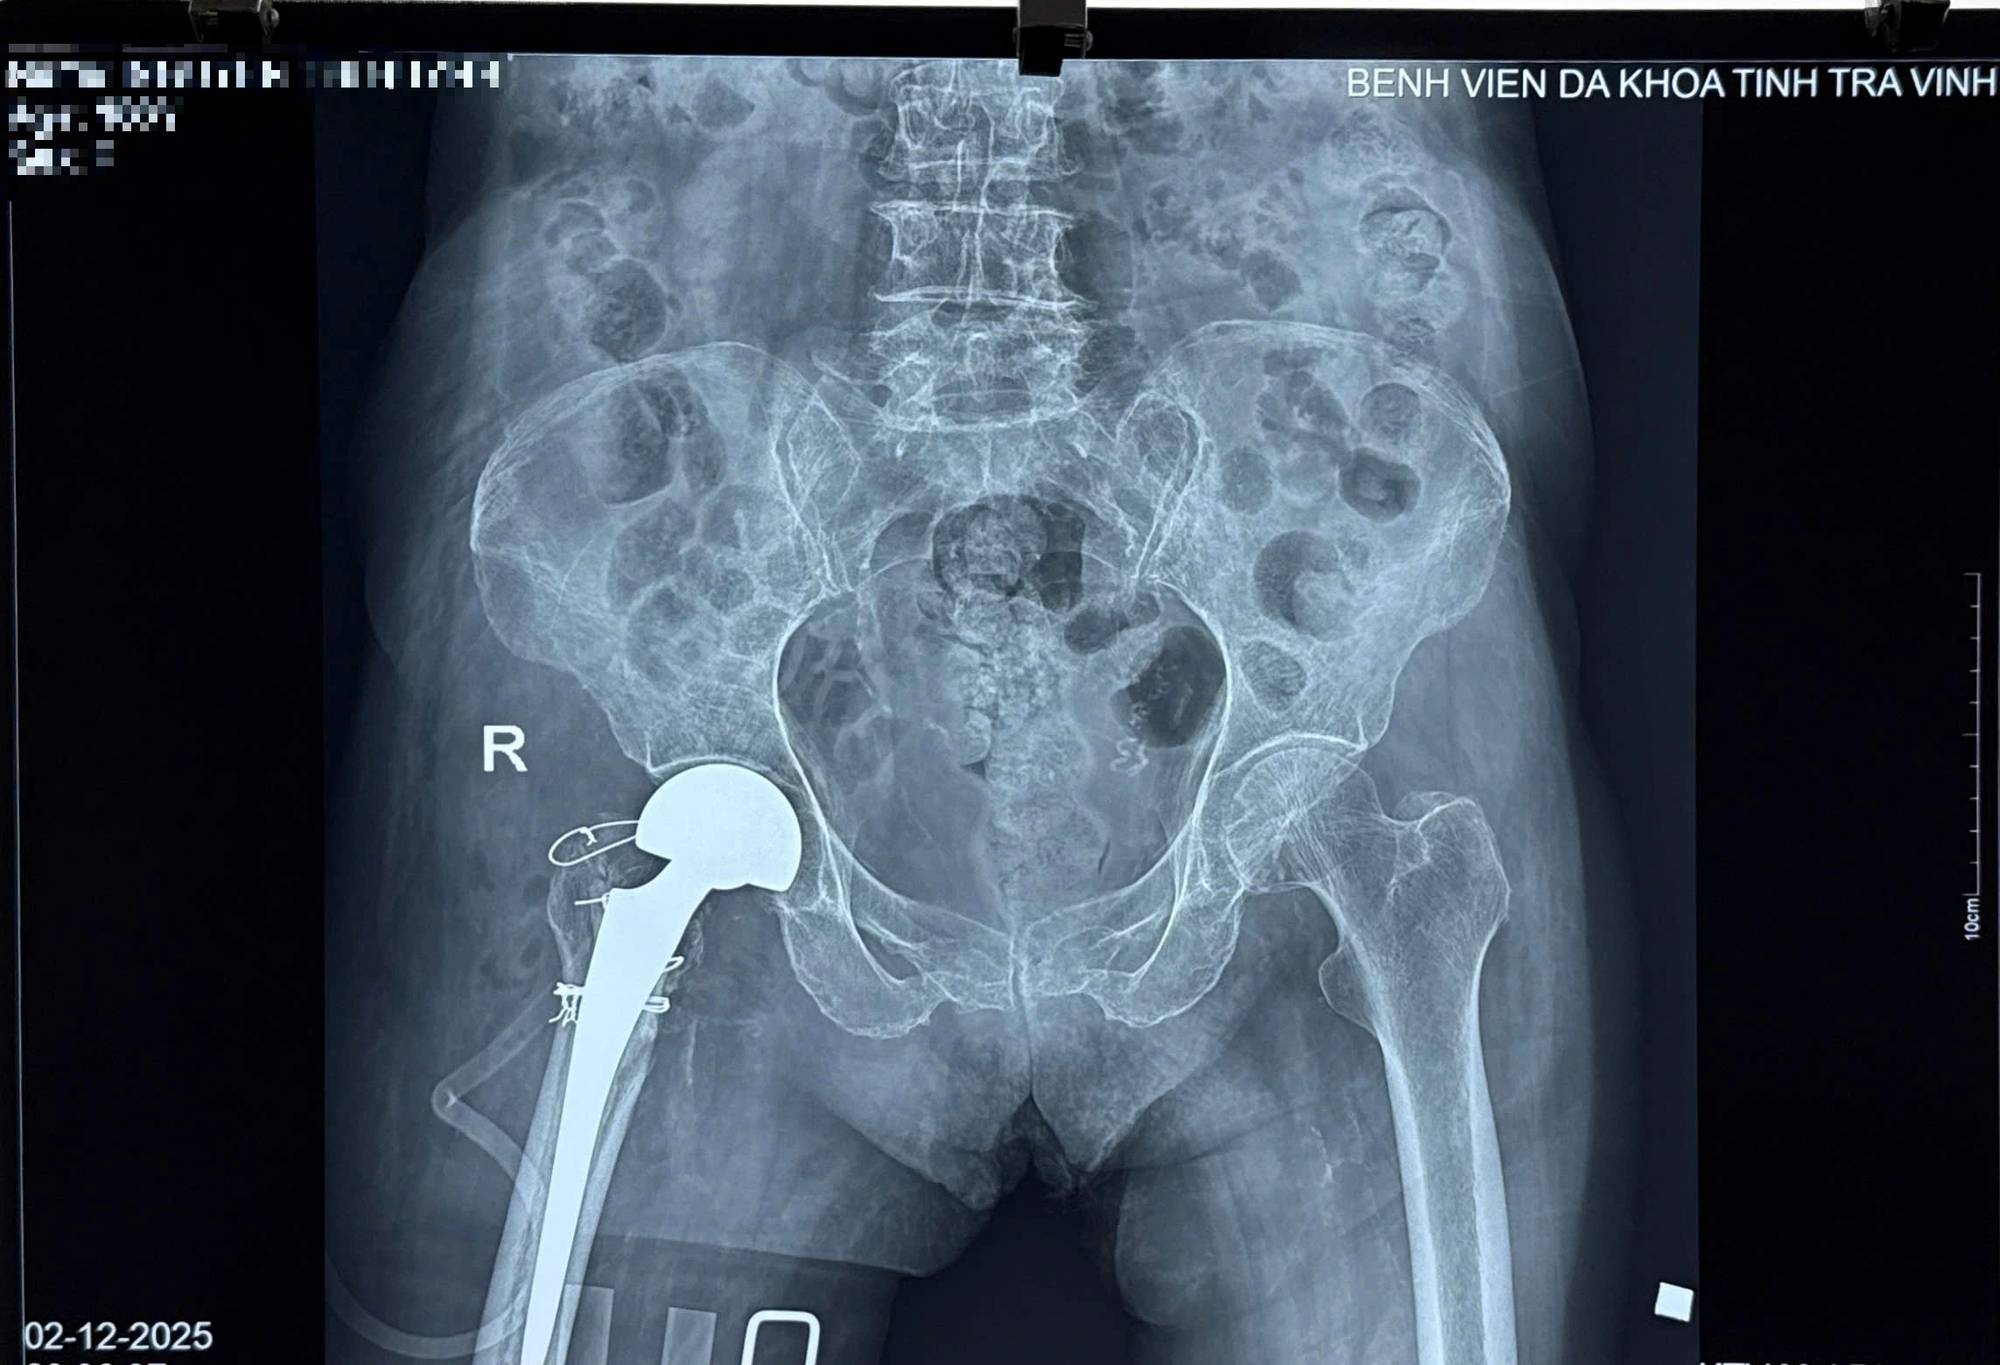

Bệnh nhân được chỉ định phẫu thuật thay khớp háng bán phần. Ca phẫu thuật diễn ra hơn 60 phút và thành công như mong đợi. Đặc biệt, đây là ca thay khớp háng đầu tiên cho bệnh nhân đến 100 tuổi.

Hình X-quang sau khi thay khớp háng thành công cho cụ bà 100 tuổi

ẢNH: NAM LONG

Sau phẫu thuật thay khớp háng 3 ngày, bệnh nhân hết đau, tập ngồi vận động tại giường, đến ngày thứ 5 tập đứng trên khung và ra viện.